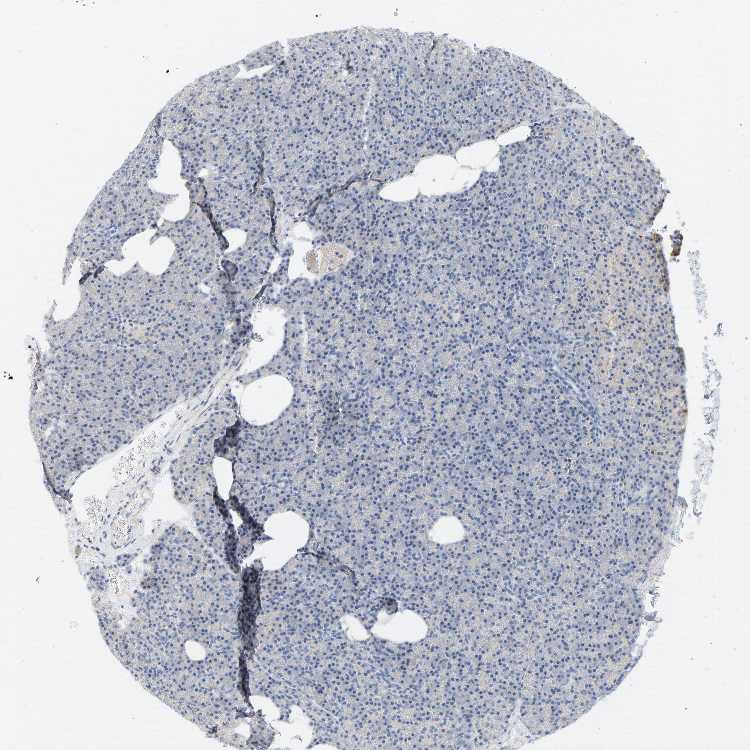

PANCREAS - Antibody stainingi

Antibody staining in the annotated cell types in the current human tissue is reported as not detected, low, medium, or high, based on conventional immunohistochemistry profiling in selected tissues. This score is based on the combination of the staining intensity and fraction of stained cells.

Each image is clickable and will lead to virtual microscopy that enables deeper exploration of all samples and also displays staining intensity scores, fraction scores and subcellular localization as well as patient and tissue information for each sample.

Antibody HPA014788Antibody HPA018176

Exocrine glandular cells MediumLow

Pancreatic endocrine cells LowNot detected